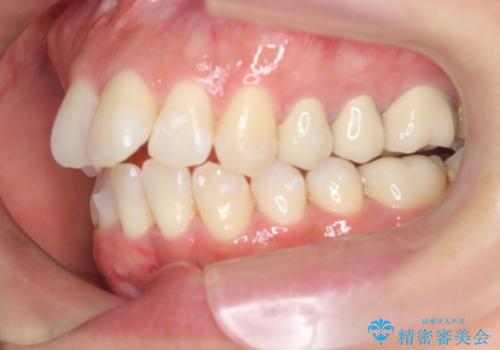

職業柄ワイヤー矯正ができない、マウスピース矯正で行う八重歯抜歯症例

- 「長年気になっている八重歯を矯正治療で治したい、ただし職業柄ワイヤー矯正は絶対にできないのでマウスピース矯正を希望。」

、と矯正治療を希望され来院されました。

通常は八重歯の抜去は行わず、小臼歯の抜去を行いワイヤー矯正を行いますが、八重歯を抜去することでマウスピースで現実的に達成できる機能的な歯並びを獲得できるよう治療計画を立案します。

治療に制約がある場合でも、現実的な治療ゴールを設定することで機能的・審美的な歯並びを手に入れることができました。